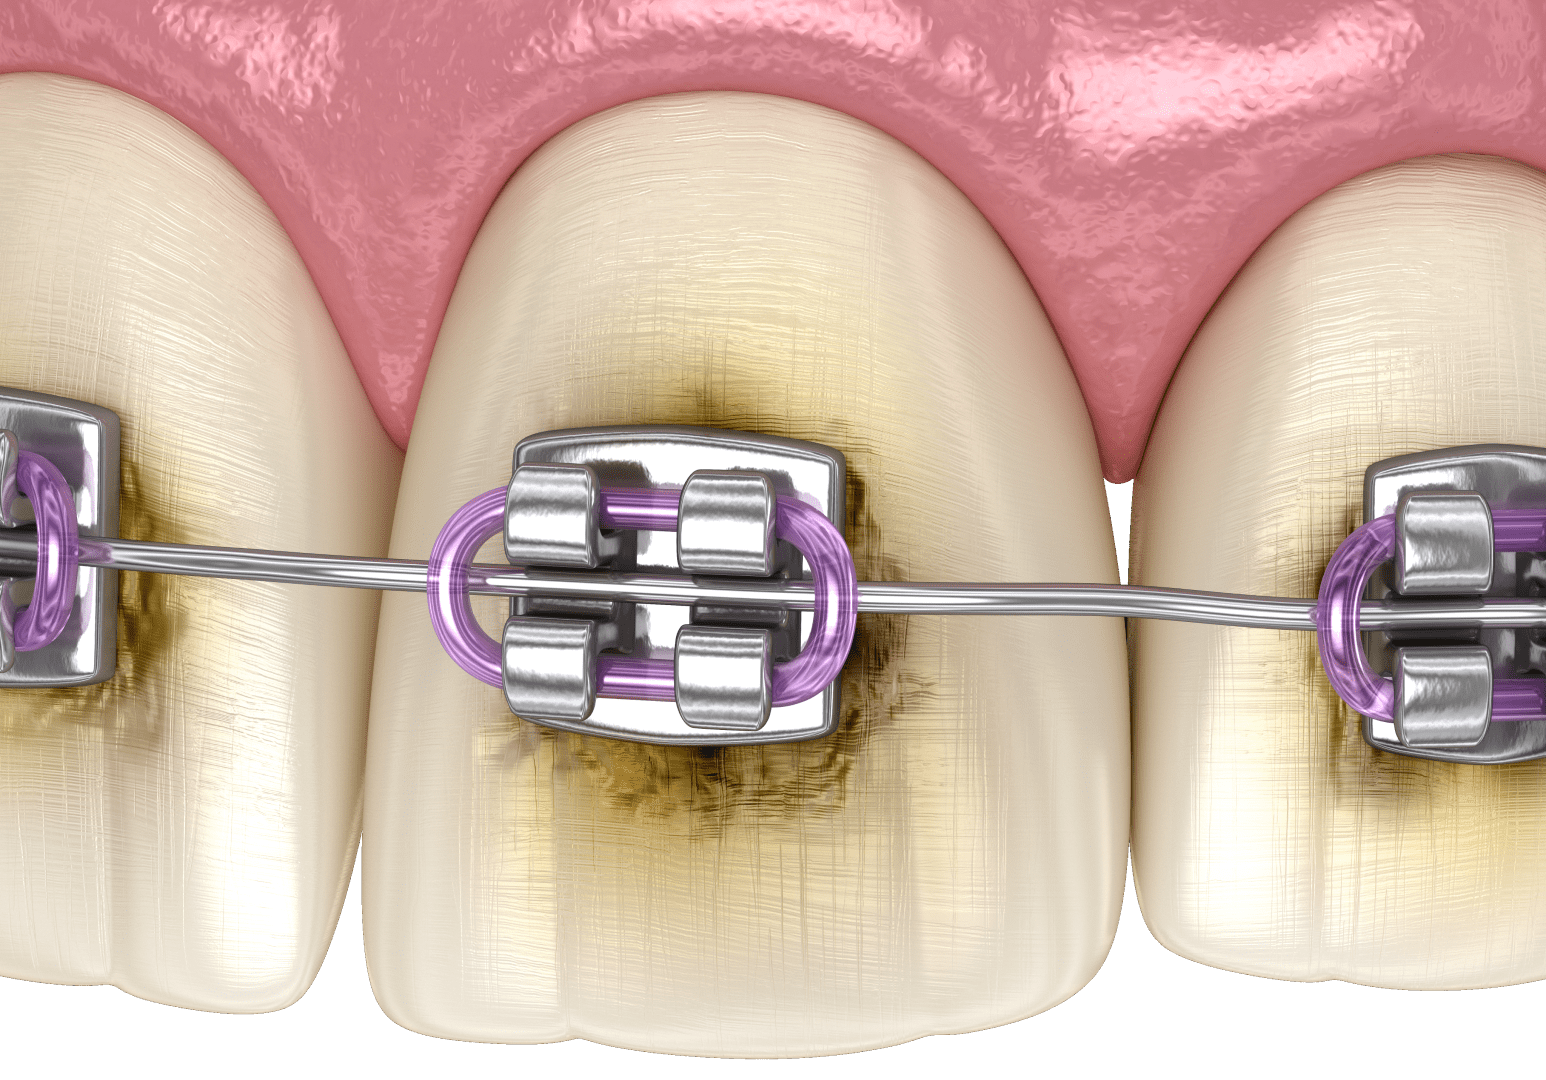

- порушення прикусу, через які деякі ділянки складніше очищувати;

На стадії поверхневого карієсу починається руйнування емалі. У місці, де раніше була світла пляма, поверхня зуба стає шорсткою, можуть з’являтися темні ділянки. У деяких випадках пацієнт починає відчувати підвищену чутливість зубів до холодної, гарячої або солодкої їжі.